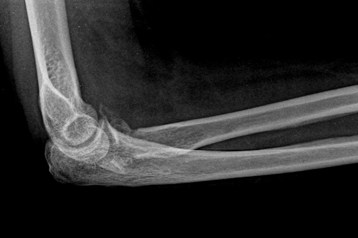

Before Surgery

Non-Union of Distal Humerus Elbow Fracture